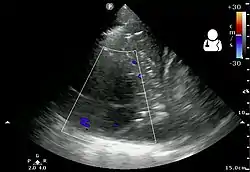

The initial investigations for suspected empyema remains chest X-ray, although it cannot differentiate an empyema from uninfected parapneumonic effusion.[5] Ultrasound must be used to confirm the presence of a pleural fluid collection and can be used to estimate the size of the effusion, differentiate between free and loculated pleural fluid and guide thoracocentesis if necessary. Chest CT and MRI do not provide additional information in most cases and should therefore not be performed routinely.[6] On a CT scan, empyema fluid most often has a radiodensity of about 0-20 Hounsfield units (HU),[7] but gets over 30 HU when becoming more thickened with time.[8]

13. 1 2 3 4 "UOTW #28 - Ultrasound of the Week". Ultrasound of the Week. 3 December 2014. Archived from the original on 9 May 2017. Retrieved 27 May 2017.